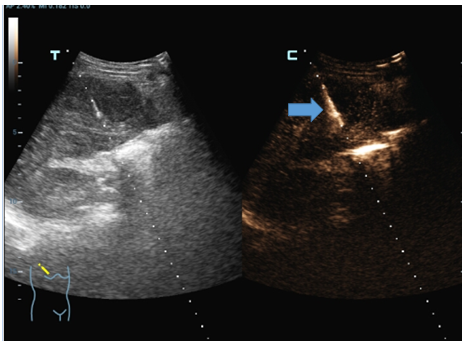

李先生今年45岁,因腹部胀满、疼痛长达一个月,来到德州市第二人民医院就诊。经核磁检查发现,肝右叶有结节,门诊建议进一步检查或穿刺活检明确诊断。随后,李先生做了常规超声检查,但未显示出肝内结节,医生建议行超声造影引导下穿刺活检。在征得李先生同意后,超声医学科主任石洪柱为李先生做了肝脏超声造影,检查历时10分钟,过程中无不适反应。通过超声造影检查发现了肝脏结节,符合恶性肿瘤表现,在超声造影引导下行结节穿刺活检术,最终为李先生明确诊断为肝细胞癌。

“相较于CT、核磁的增强扫描,超声造影能定量评估器官、组织及病灶局部血流灌注情况,造影剂通过肺循环呼出体外,不进入组织间隙,更适合心、肝、肾功能不全者以及不能耐受其他造影检查的患者,无创伤、无辐射、使用方便、实时显像、时间短、可重复。”石洪柱介绍,超声造影优势多、用途广,可用于器官或组织肿块的定位、定性,血管内病变及斑块活性的诊断,输卵管、输尿管、胆道等管腔通畅性的判断,介入超声穿刺的引导,肿瘤消融、化疗、放疗治疗效果的评估,外伤或出血性病变的出血情况的评估,心腔、心肌、血管、血流动力学病变的诊断等。